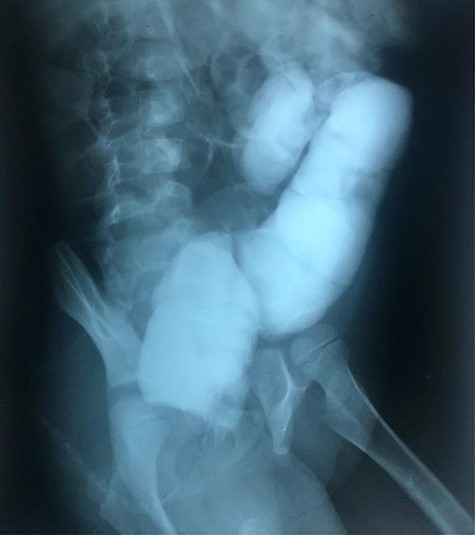

The clinical case consisted of a 4-year-old female patient who presented with long-standing constipation, which afflicted her since birth. The mother referred that the patient could only defecate 2 to 3 times per week, requiring the administration of rectal enemas, lactulose and plum juice. Upon physical examination, the patient presented increased frequency of intestinal sounds, no abdominal tenderness on palpation, tympanic sound to percussion, abdominal distention and a positive blast sign. A water-soluble contrast enema was performed to evaluate the colonic segments and rectum. The study displayed a distal narrow segment with proximal distention representing the pathognomonic transitional zone (Figs 1 and 2). Rectal biopsies were taken at 3, 5 and 10 cm from the anal margin. The biopsy at 3 cm showed hyperplasia of the muscularis mucosae and absence of the submucosal and myenteric nerve plexuses. However, the other two segments that were taken showed no abnormal findings. According to these findings, the patient was diagnosed with USHD. Treatment consisted of transanal myectomy of the internal anal sphincter.

Radiographic abdominal lateral view of water-soluble contrast enema.